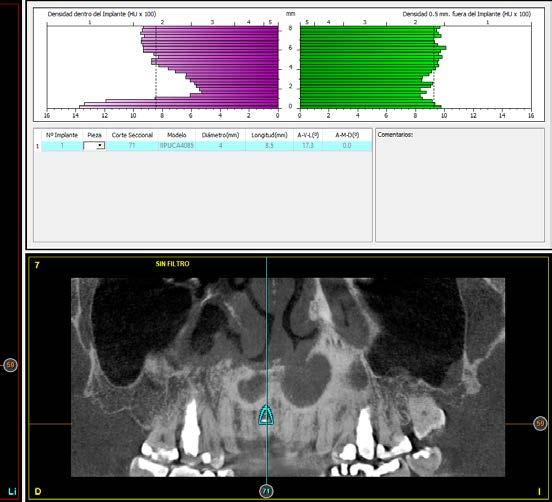

radiografía panorámica inicial para el diagnóstico nos aporta una imagen radiolucida entorno al ápice del diente en posición 11 ( Figura 1 ). Para conocer mejor el alcance de la lesión y las opciones terapéuticas de las que disponemos se lleva a cabo un cone-beam en el que se puede objetivar de forma precisa el defecto apical al diente. Este defecto es circunferencial y está dejando una reabsorción casi completa de la tabla ósea vestibular y parcial de la palatina, con un grosor de 1.9 mm, como vemos en el corte seccional (Figura 2). Si observamos la medida total en la zona media del incisivo dentral, necesitamos cubrir una anchura aproximada de 8 mm por lo que el implante que coloquemos irremediablemente dejará un gap, que según los protocolos quedará en vestibular. Utilizando una plataforma estándar de 4.1 mm el gap a rellenar será prácticamente de 4 mm según las medidas que nos

Figura 2. Corte seccional del cone-beam

arroja el cone-beam de planificación. Utilizaremos además un implante de longitud mayor que la que se emplearía para un incisivo central en una zona edéntula, para lograr un anclaje apical que nos dé la estabilidad necesaria en la colocación del implante y

nos permita la carga inmediata posterior. En este caso 11.5 mm (Figura 3 y 4).Una vez diagnosticado el caso de forma correcta con las imágenes del cone-beam iniciamos la fase quirúrgica. Realizamos la exodoncia del diente 11 con el menor trauma

Figura 3. Diámetro del alveolo tras la exodoncia del diente 11.

Figura 4. Planificación del implante de plataforma universal con una longitud que nos permita anclarnos apicalmente.